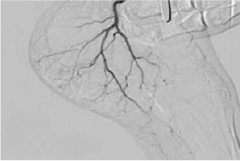

- Image-guided heel pain treatment using fluoroscopy or ultrasound.

- Embolic injection to block the blood vessels causing inflammation in the plantar fascia.